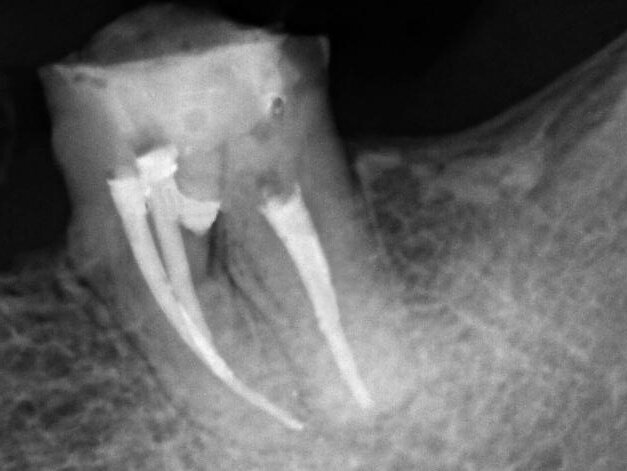

Female patient, 47 years old, presented with a clinical picture of extensive iatrogenic perforation of the furcation region of the dental element 36 (Figs. 1 and 2), associated with radiographic bone loss, vestibular fistula and pain on palpation. The patient reported history of having been previously subjected to an urgent intervention in this tooth by other professional, as it presented acute pain characteristic of pulpitis.

Fig. 1: Initial clinical and radiographic appearance of teeth 36

Fig. 2: Initial clinical and radiographic appearance of teeth 36